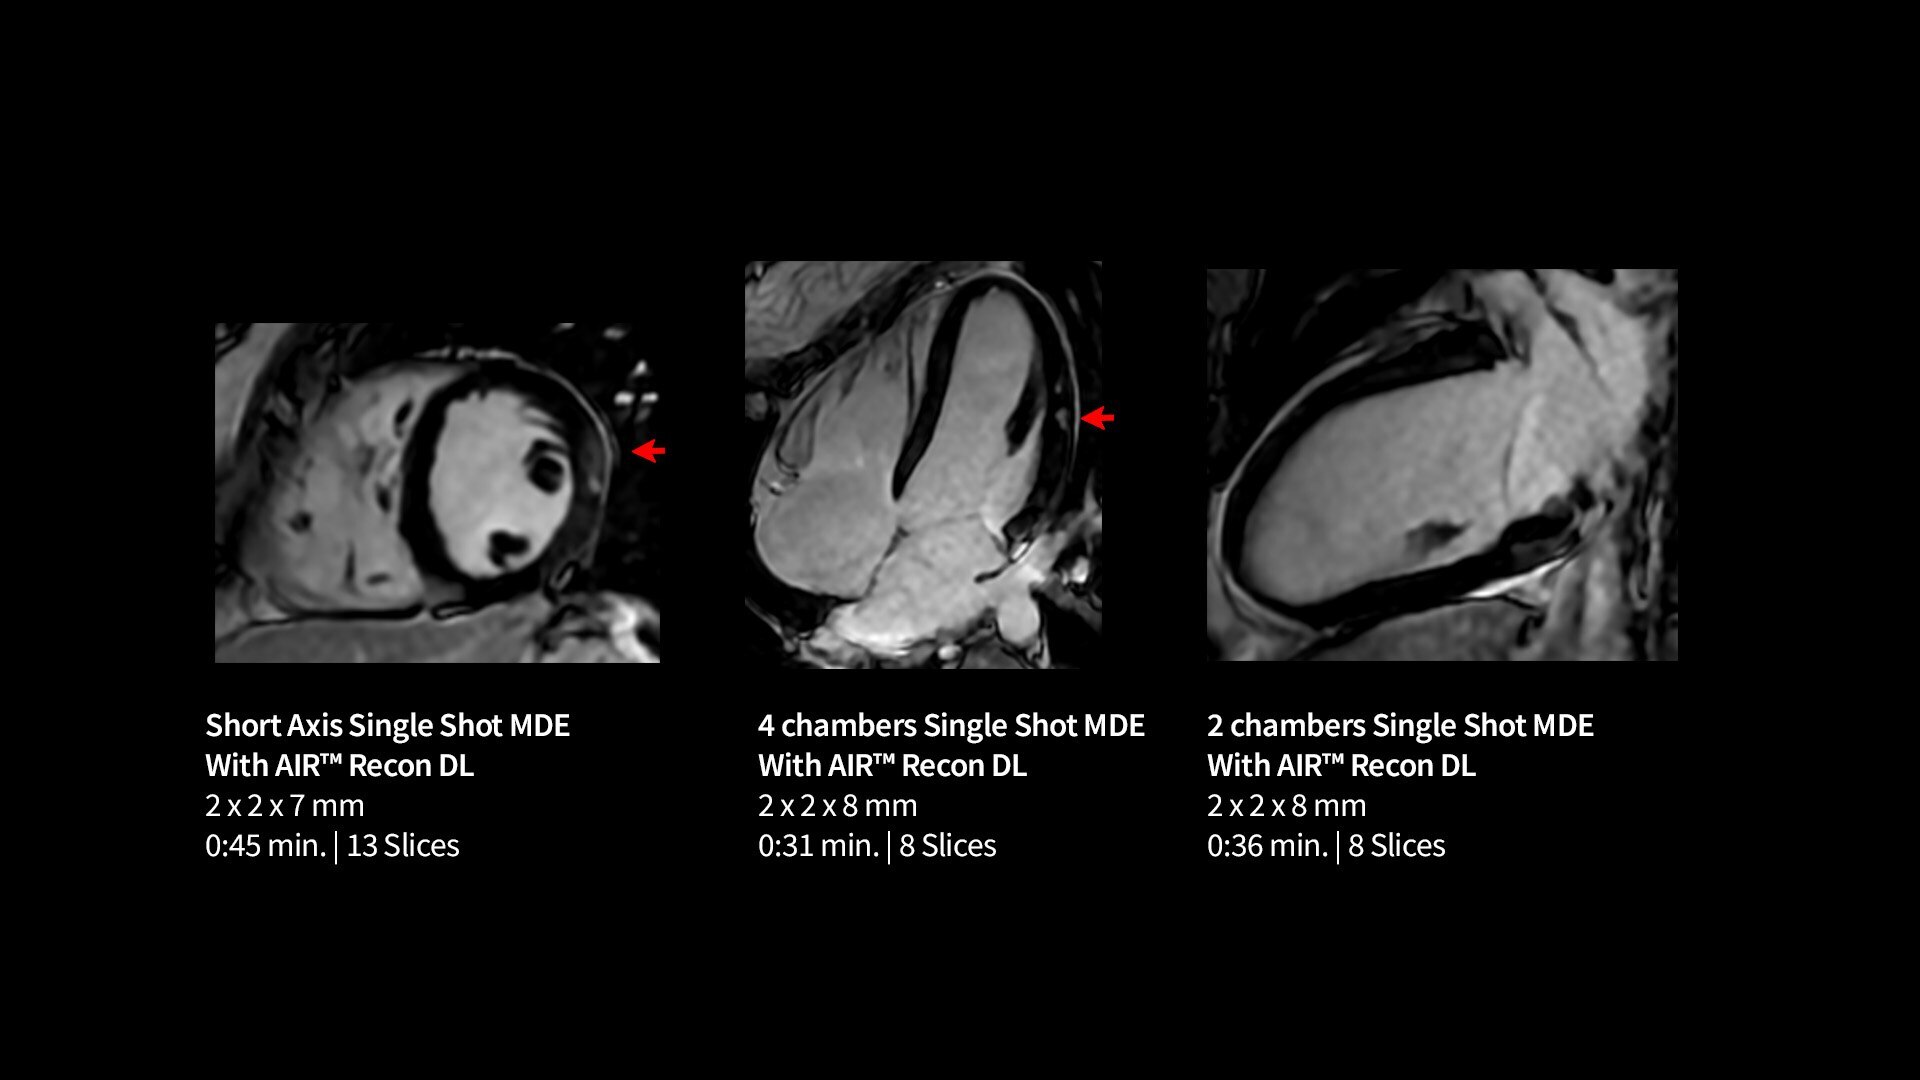

Every step of our cardiac MR assessment is compatible with our pioneering deep-learning algorithms, including: morphology, function, perfusion, mapping and myocardial viability with

late enhancement.

Your teams can capture clarity with AIR™ Recon DL, a revolutionary technique to boost image quality, providing accurate anatomic information and advanced soft tissue contrast. It’s already transformed the lives of millions of patients worldwide since 2021. Thanks to Sonic DL™ they can also now assess cardiac viability faster than ever before, with as little as 15 to 20 minutes per scan.*†